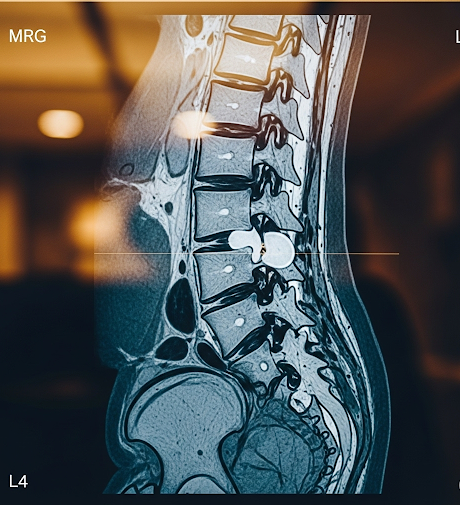

- 정확한 진단 및 평가: MRI, X-ray 등 정밀 영상 검사와 신경학적 검사를 통해 디스크의 위치, 정도, 신경 압박 여부를 정확히 파악하는 것이 중요합니다.

정밀 MRI 검사를 통해 디스크 상태를 정확히 진단합니다.